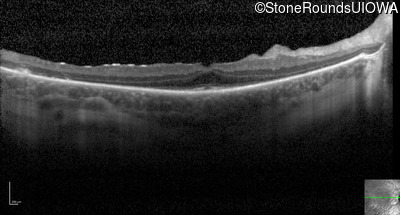

Optical Coherence Tomography - Left - 20/40

Exemplar / OCT Stack